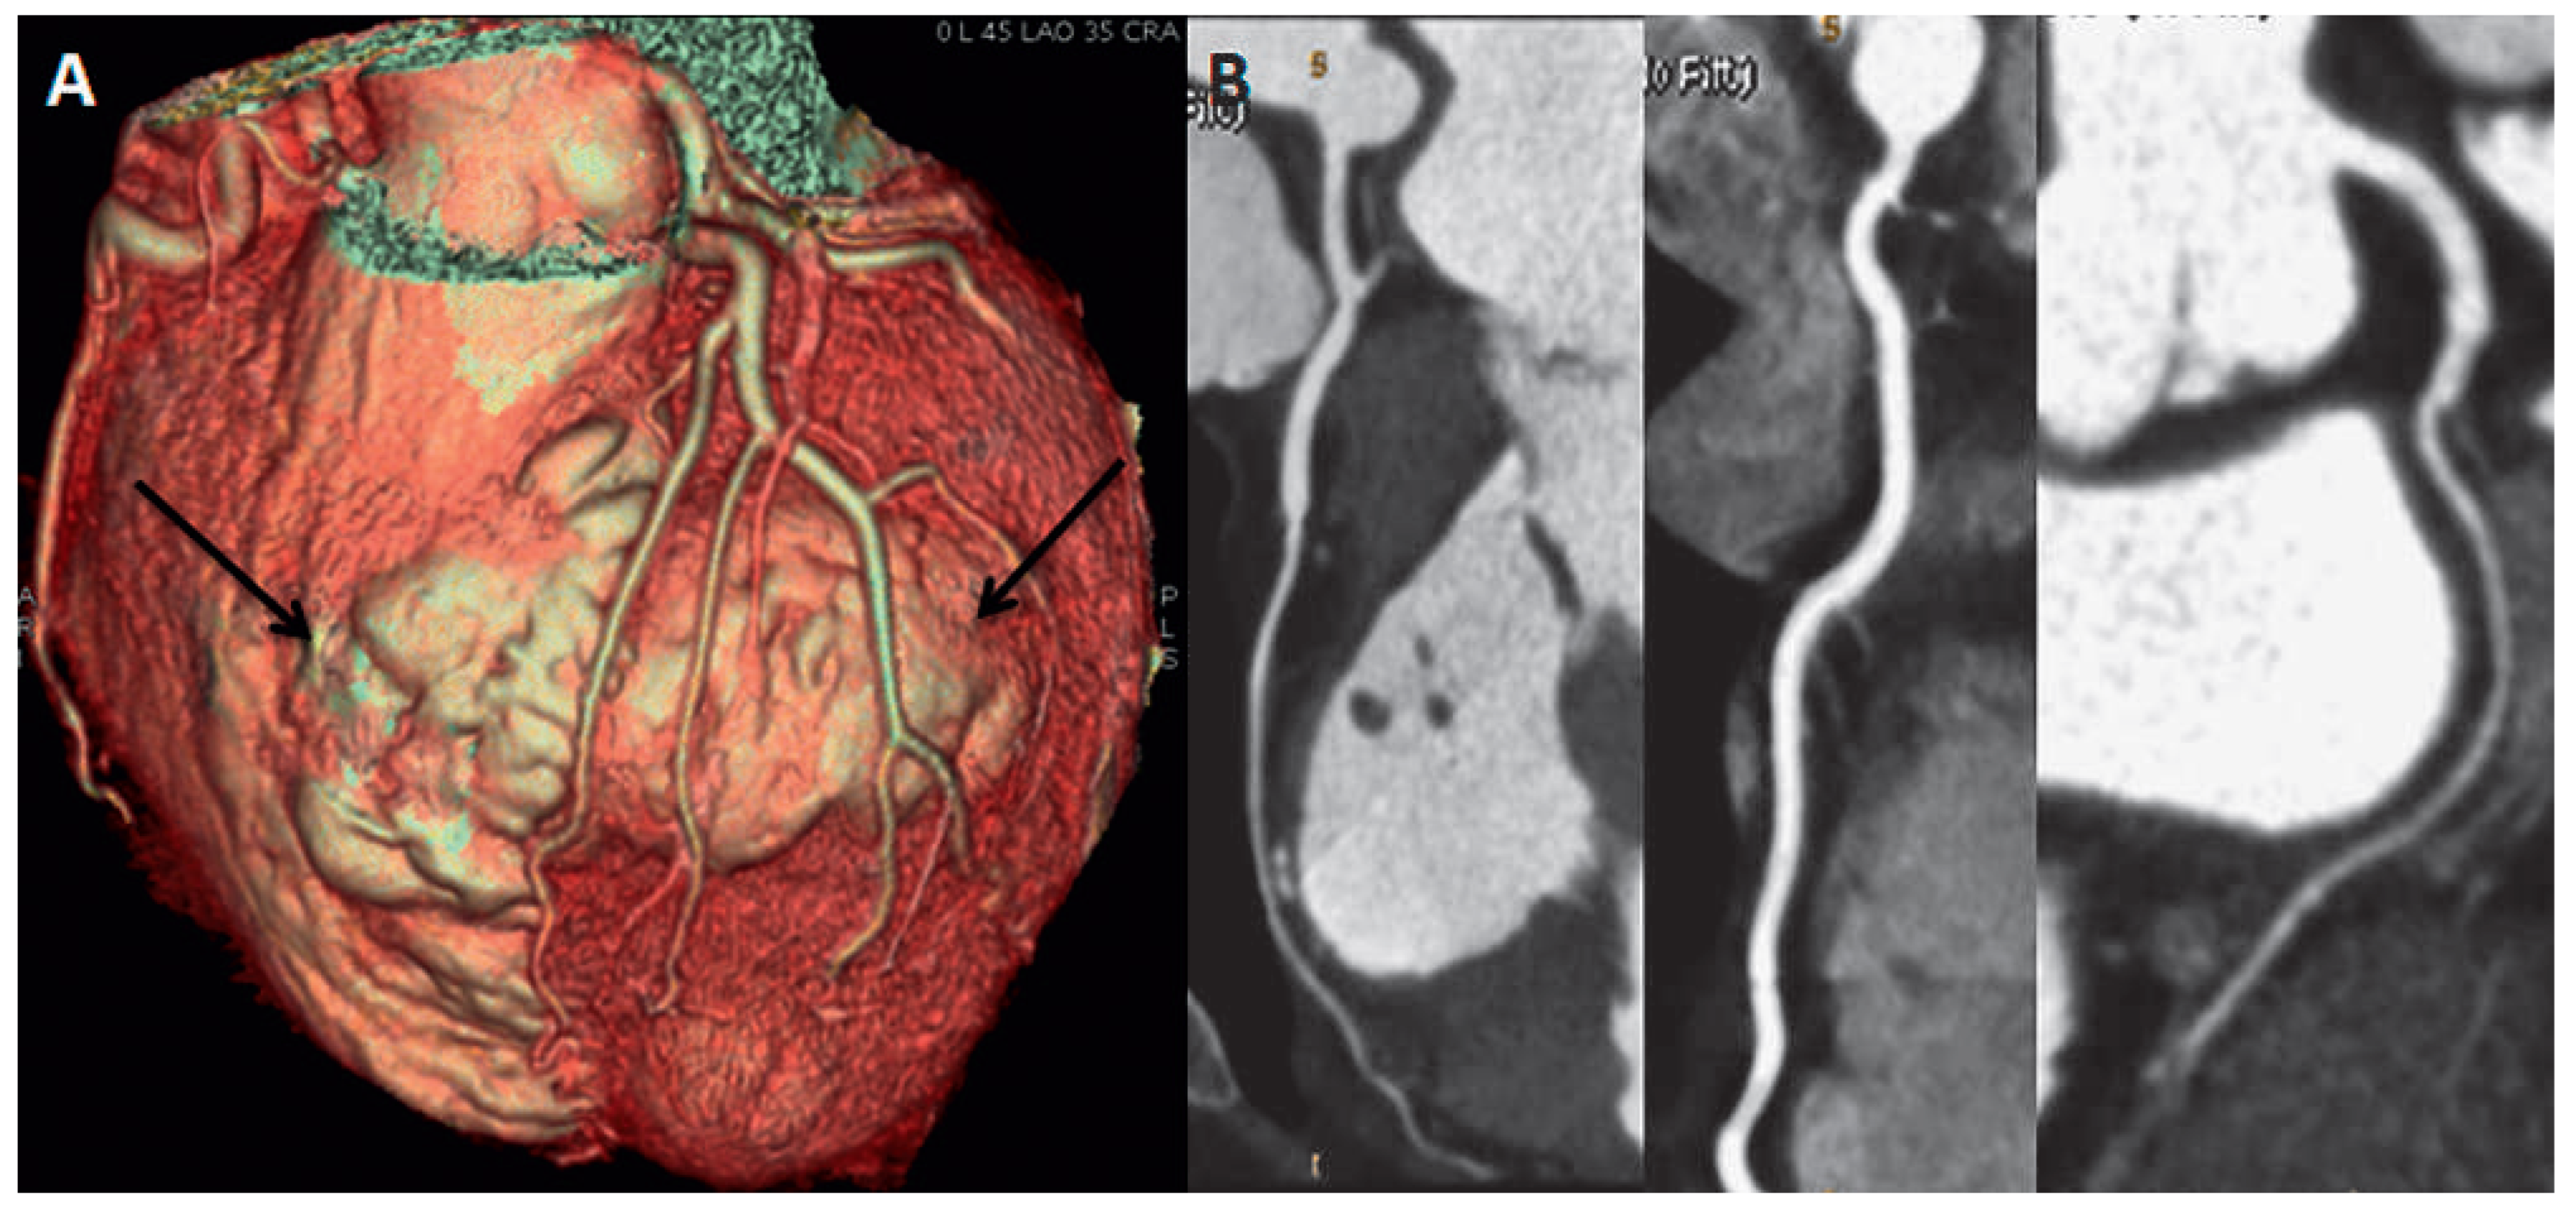

However, the patient’s recordings revealed that radiotherapy was performed in supraclavicular and axillary regions, without irradiation of mediastinum (Figure 4). According to the recordings the cumulative radiation dose was 47.5 Gy divided into 23 sessions. Another possible cause of LV bulging could be a diverticulum. However, its wall should contain endocardium, myocardium and pericardium and display normal contraction [2]. On the contrary in our case, MRI showed akynetic region with transmural LGE, which excludes the presence of normal myocardium and consistent with transmural scar. Cardiac sarcoidosis is another rare cause of aneurysm formation in the heart [3]. However, the previous serial PET investigations performed in the follow-up setting of the breast cancer never showed any pathological uptake either in the lungs or in the heart. From the old patient recordings we were able to recover the ECG of 2005 which showed the similar findings as the ECG on the index event.

Figure 4. The picture from the patient’s recordings from 1985 showing the region of radiotherapy application (arrows).